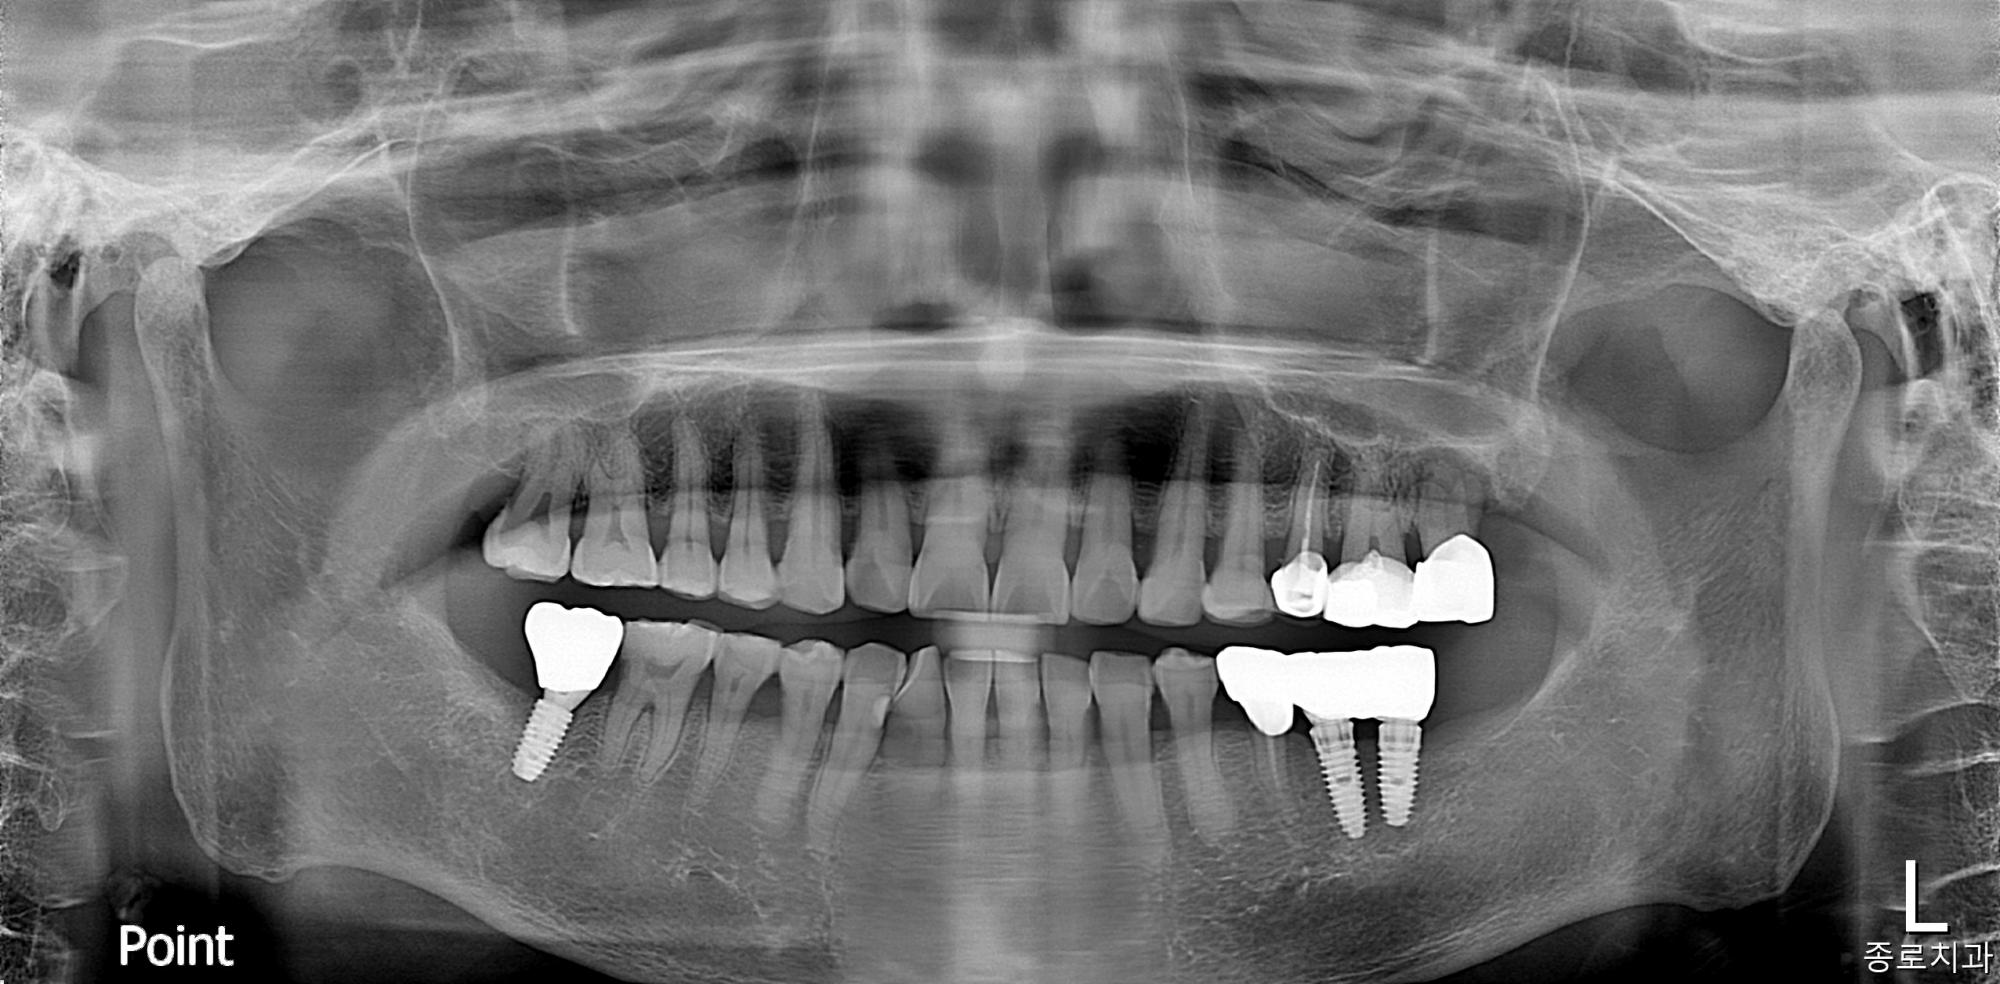

전/후 사진

임플란트

치료 전

치료 후